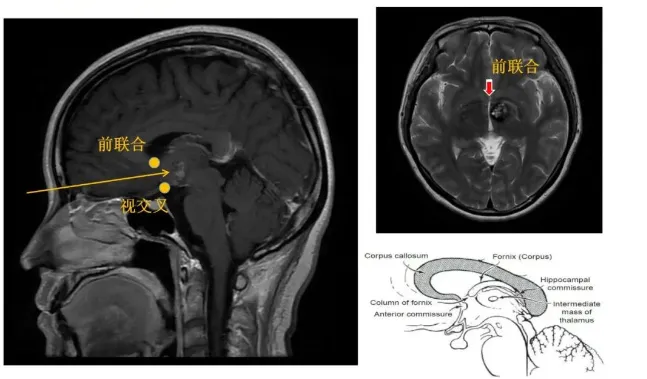

为确保手术的精准与安全,巴特朗菲教授制定了周密的手术方案:采用额底纵裂经终板入路实施丘脑占位切除术,全程配合MEP+SEP神经电生理监测,实时监测神经功能状态。由于肿瘤位置深在,术中导航易因脑脊液释放引发漂移,巴特朗菲教授还将前联合作为关键解剖标记,精准定位肿瘤位置——它正位于前联合后方。

所采用的经纵裂入路,是利用大脑纵裂的自然间隙进入深部病灶,能最大限度降低对脑组织的牵拉和侵犯,但该操作通道深且狭窄,每一步操作均需极致的精细。